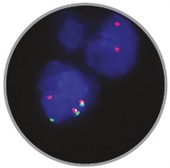

- In Situ Hybridization

- Clinical Flow Cytometry